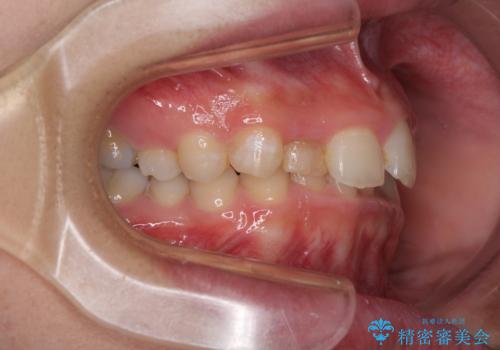

- 前歯の歯並びと不自然な色をした前歯のクラウンを気にして来院された患者様です。

上下前歯の歯列不正はインビザラインにより歯列を整え、その後に、前歯をオーダーメイドタイプのオールセラミッククラウンにて補綴治療することとしました。

前歯のデコボコを一番気にしていらっしゃいましたが、矯正治療により下顎前歯が隠れるほどのディープバイトも一緒に改善され、奥歯に負担のかかりにくい咬み合わせとなりました。